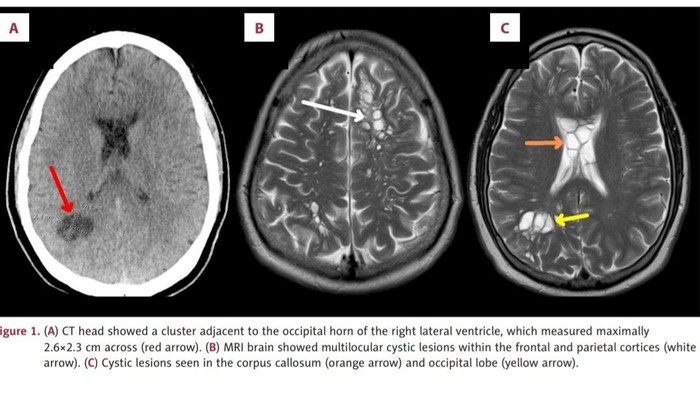

Hasilnya, terlihat banyak kista di kedua sisi otaknya dan ada pembengkakan. Dia didiagnosis terkena infeksi parasit neurocysticercosis (NCC).

Kondisi ini menggambarkan saat kista larva, kantung tertutup yang berisi parasit yang belum matang, dari cacing pita babi menginfeksi bagian tubuh dan menyebabkan peradangan.